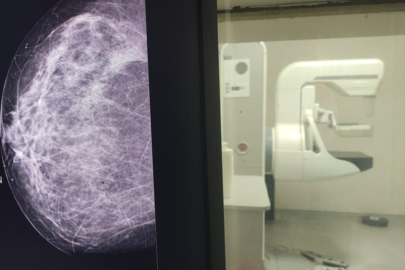

Yalnızca 5 dakika ayırıp çektirdiği mamografi sayesinde meme kanserinin erken evrede teşhis edildiğini vurgulayan Dr. Yavuz, o 5 dakikanın tüm hayatını etkileyen olumlu sonuçlara yol açtığını belirtti.

Sağlıklı hayat merkezi bünyesinde meme kanserine yönelik; taramaların, elle muayenenin ve erken teşhisin önemi gibi konularda vatandaşlara yönelik eğitimler gerçekleştirdiklerini vurgulayan Dr. Yavuz, “Kendim 47 yaşındayım bu sürece kadar 2 kere mamografim olması gerekirken ben bu mamografiyi çektirmedim. Araya korkularım girdi, kaygılarım girdi, hayatımdan önemli olmayan sebepler girdi. Bir gün röntgen teknisyeni arkadaşımızın ısrarı ile kaygılarımı, korkularımı bir kenara bıraktım. 5 dakikalık sürede gittim, mamografimi çektirdim” dedi.

Bu süreçte elle muayenede herhangi bir bulgu yaşamadığını dile getiren Dr. Yavuz, “Herhangi bir şikâyetim, semptomum da yoktu. Bana bir şey olmaz dedim ve ben mamografi çektirdiğimi unuttum. Ama görev yaptığım hizmet alanımda çekilen mamografi ile bana bi-rads 4c denilen meme kanseri öncesi tarama bulgusu tanısı konuldu. Ben bu tanıyla ileri tetkik ve tedavi yaptığımda meme kanseri ile karşılaştım” şeklinde konuştu.

Çektirdiği mamografi sayesinde erken tanı aldığını ve tedavisini tamamladığının altını çizen Dr. Yavuz, “Şu anda hayatıma sağlıklı olarak devam ediyorum. İşte o beş dakika benim tüm hayatıma yön verirken, çok olumlu sonuçlara sebep oldu. Her ay yapacağınız bir elle meme muayenesi sizin hayatınızı tanımanızda, çektireceğiniz mamografi de tanınızın erken olmasına sebep olacak. Ben hekim olarak bunu yaptım. Kendi birimimde bunu başarabildim. Sizleri de her zaman KETEM birimlerinde mamografinizi çektirmeye davet ediyoruz” ifadelerini kullandı.